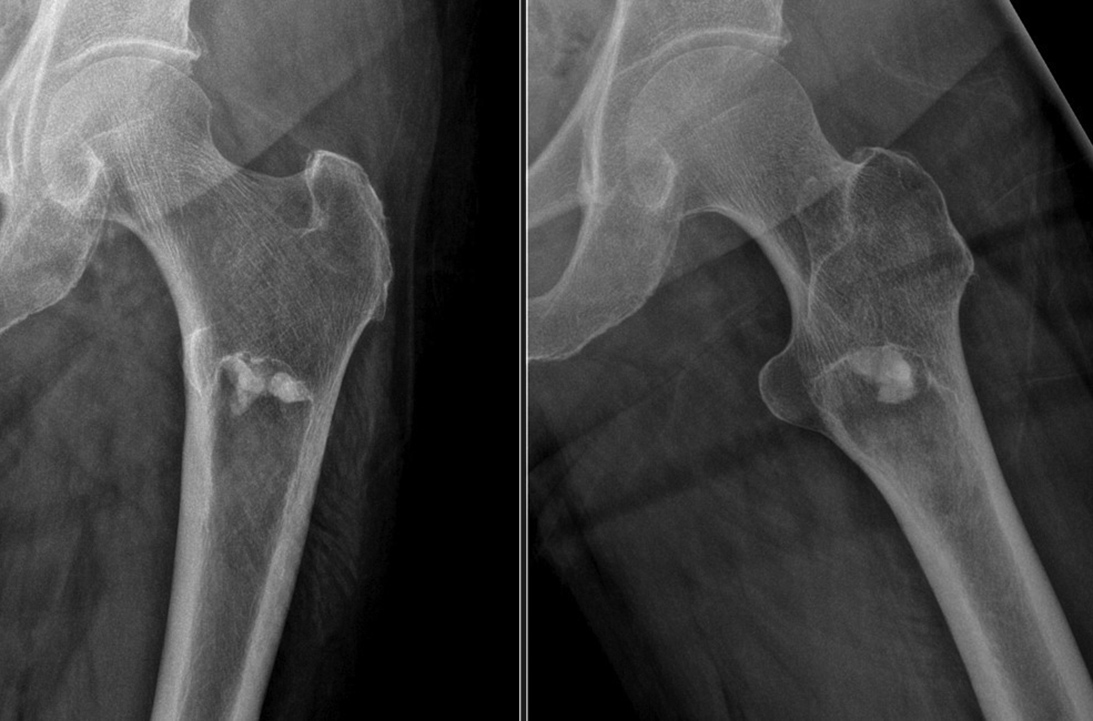

• Bone-RADS is a novel scoring system to differentiate lytic bone lesions

Alec Bigness, MD; Jamie Caracciolo, MD; Odion Binitie, MD, FAAOS

Orthopaedic surgeons often encounter radiographic findings that raise concern for undiagnosed malignancies, with diagnoses ranging from benign bone cysts to metastases or primary bone tumors.